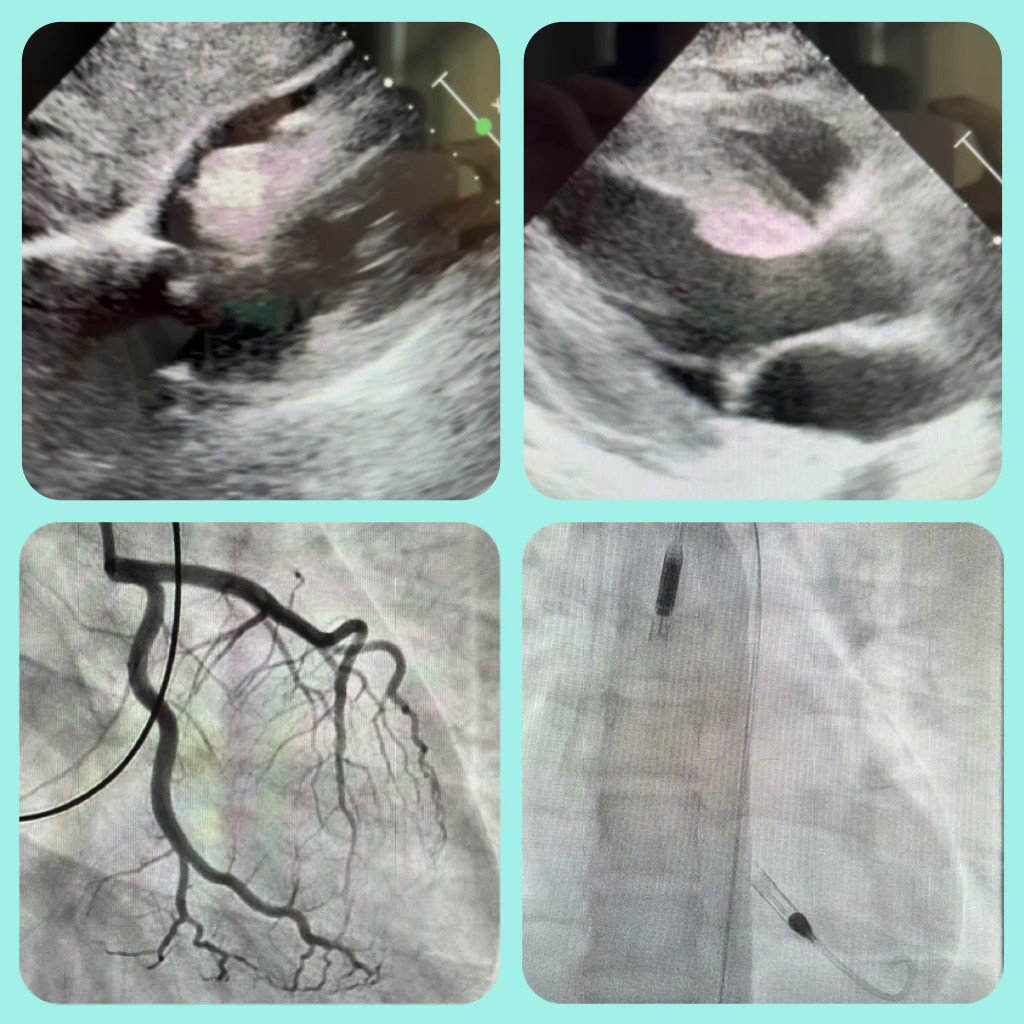

"#ACCIC #EAPCI @APSIC6 @SCAI @CCIJournal 20F in cardiogenic shock 🎥Echo: moderate pericardial eff + THICK & severely impaired LV 🛢RHC: CI 1.9L, EDP 32, PAP 36 Coronaries: normal 🚰Tap: no improvement in BP 2 pressors & Impella CP 💭 Thoughts? @agtruesdell @DrAmirKaki"